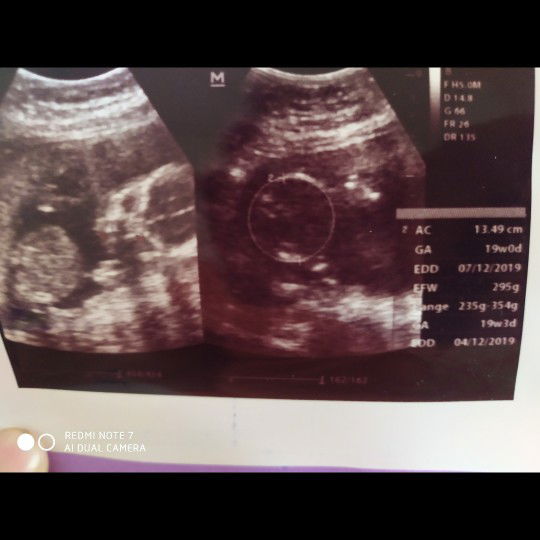

Hpl mundur ?

Bun, jadi bingung usg pertama waktu 19w hpl nya tgl 4 Desember, trus usg terakhir minggu lalu hplnya mundur tgl 7 Desember,.. kira kira ada gak yang kaya aku, hplnya ganti pas usg ? uda deg deg an nunggu debaynya kasih gelombang cinta biar cepet ketemu, tapi debaynya masih anteng di dalem, padahal udah dikasih obat perangsang kontraksi ☹